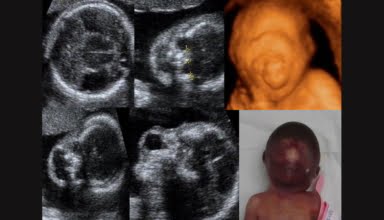

[Video] Siêu âm chẩn đoán dị tật hệ thần kinh, Bs Hà Tố Nguyên

Siêu âm chẩn đoán dị tật hệ thần kinh là bài giảng trong Khóa học Siêu âm Sản phụ khoa (BV Từ Dũ) do Bs Hà Tố Nguyên giảng dạy.